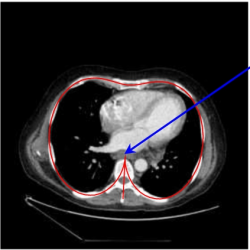

$({x_{0}},{y_{0}})$ is the starting point (the ‘spike’ point of the model, see Fig. 1).

1.

Fig. 1

An example of CT scan slice with a model curve (red line).